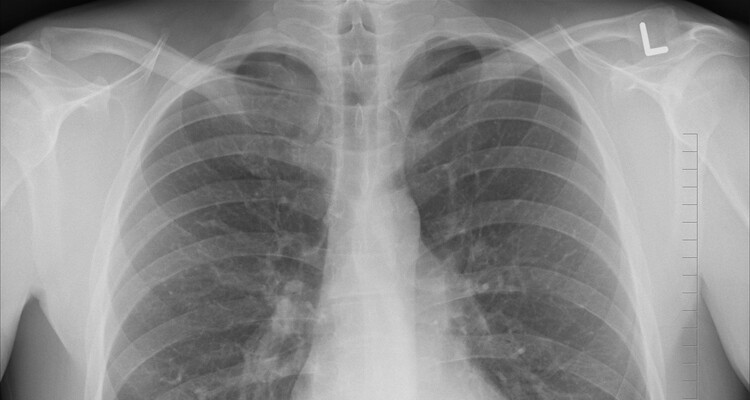

Lungenkrebs zählt zu den häufigsten und gefährlichsten Krebsarten: Er hat sich in den letzten Jahren weltweit zur Krebstodesursache Nummer 1 entwickelt. Eine der Hauptursachen ist das Rauchen. Aber auch Nicht-Raucher können betroffen sein. Früh erkannt ist eine Heilung möglich, doch ein bösartiger Tumor aus der Lunge streut rasch in andere Organe und bildet Tochtergeschwülste (Metastasen). Aus diesem Grund sind sowohl eine schnelle und umfassende Diagnostik, als auch eine effektive Zusammenarbeit vieler medizinischer Bereiche für die Behandlung von Lungenkrebs essentiell.